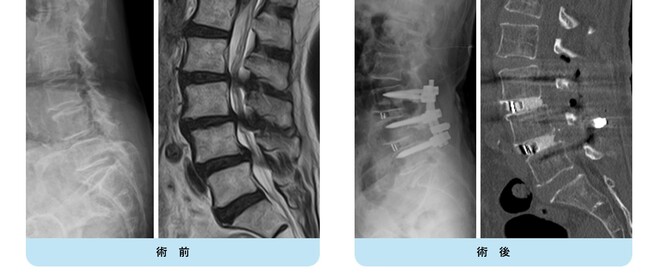

第4腰椎の前方へのすべりのため神経の圧迫を認めています。腰椎後方からずれを金属で整復固定し神経症状が改善しています。

【術前】

第2, 第3, 第4腰椎に前方への変性すべりを認めます。痛みのため背中を反って立てないことが分かります。MRIではいずれの椎間でも強い脊柱管狭窄が発生し、神経が圧迫されているのが分かります。

【術後】

スクリューとロッド、人工骨を使用した手術により腰椎の階段状変性すべりが整復され、痛みが改善したため腰を反って立つことが出来ています。第2腰椎の前方すべりは軽微であったため、金属は使わず除圧術のみに留めています。